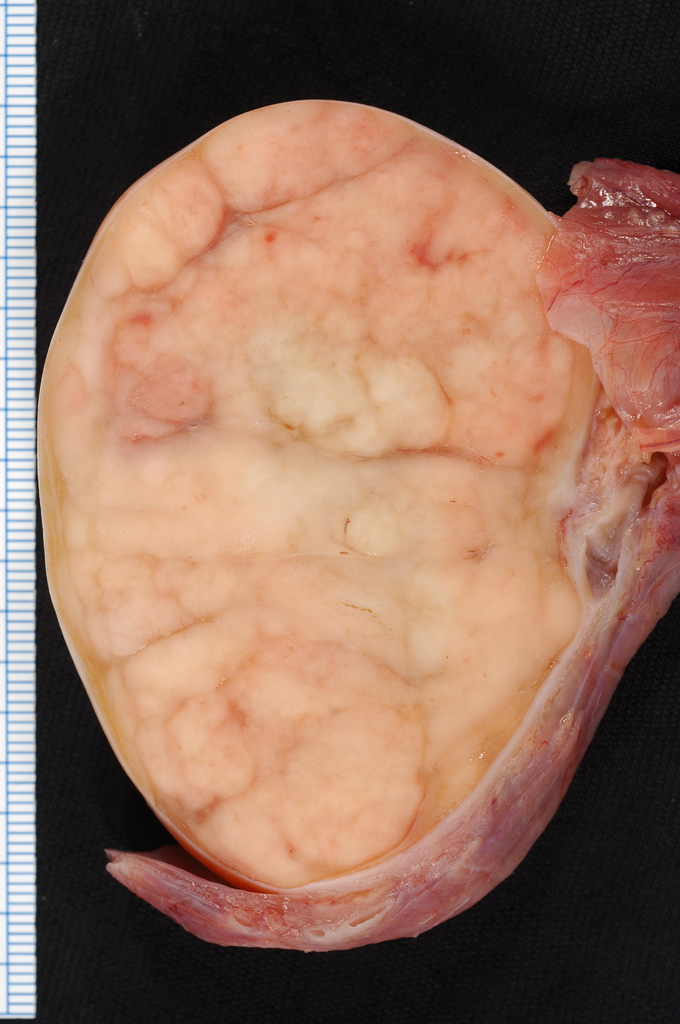

Germ cell tumours (GCTs)

Germ cells are the cells in the testes that generate sperm, and 90% of all testicular cancer originates from these cells. Germ cell tumours (GCTs) are divided into two categories:

- Seminomas – in comparison with other testicular cancers, seminomas grow and spread at a relatively slow rate.

- Non-seminomas – these tumours grow faster than seminomas, and are common in men whose ages range from their late teens to early 30s.

- Lumps and nodules (smooth, rounded masses) in one or both of the testes